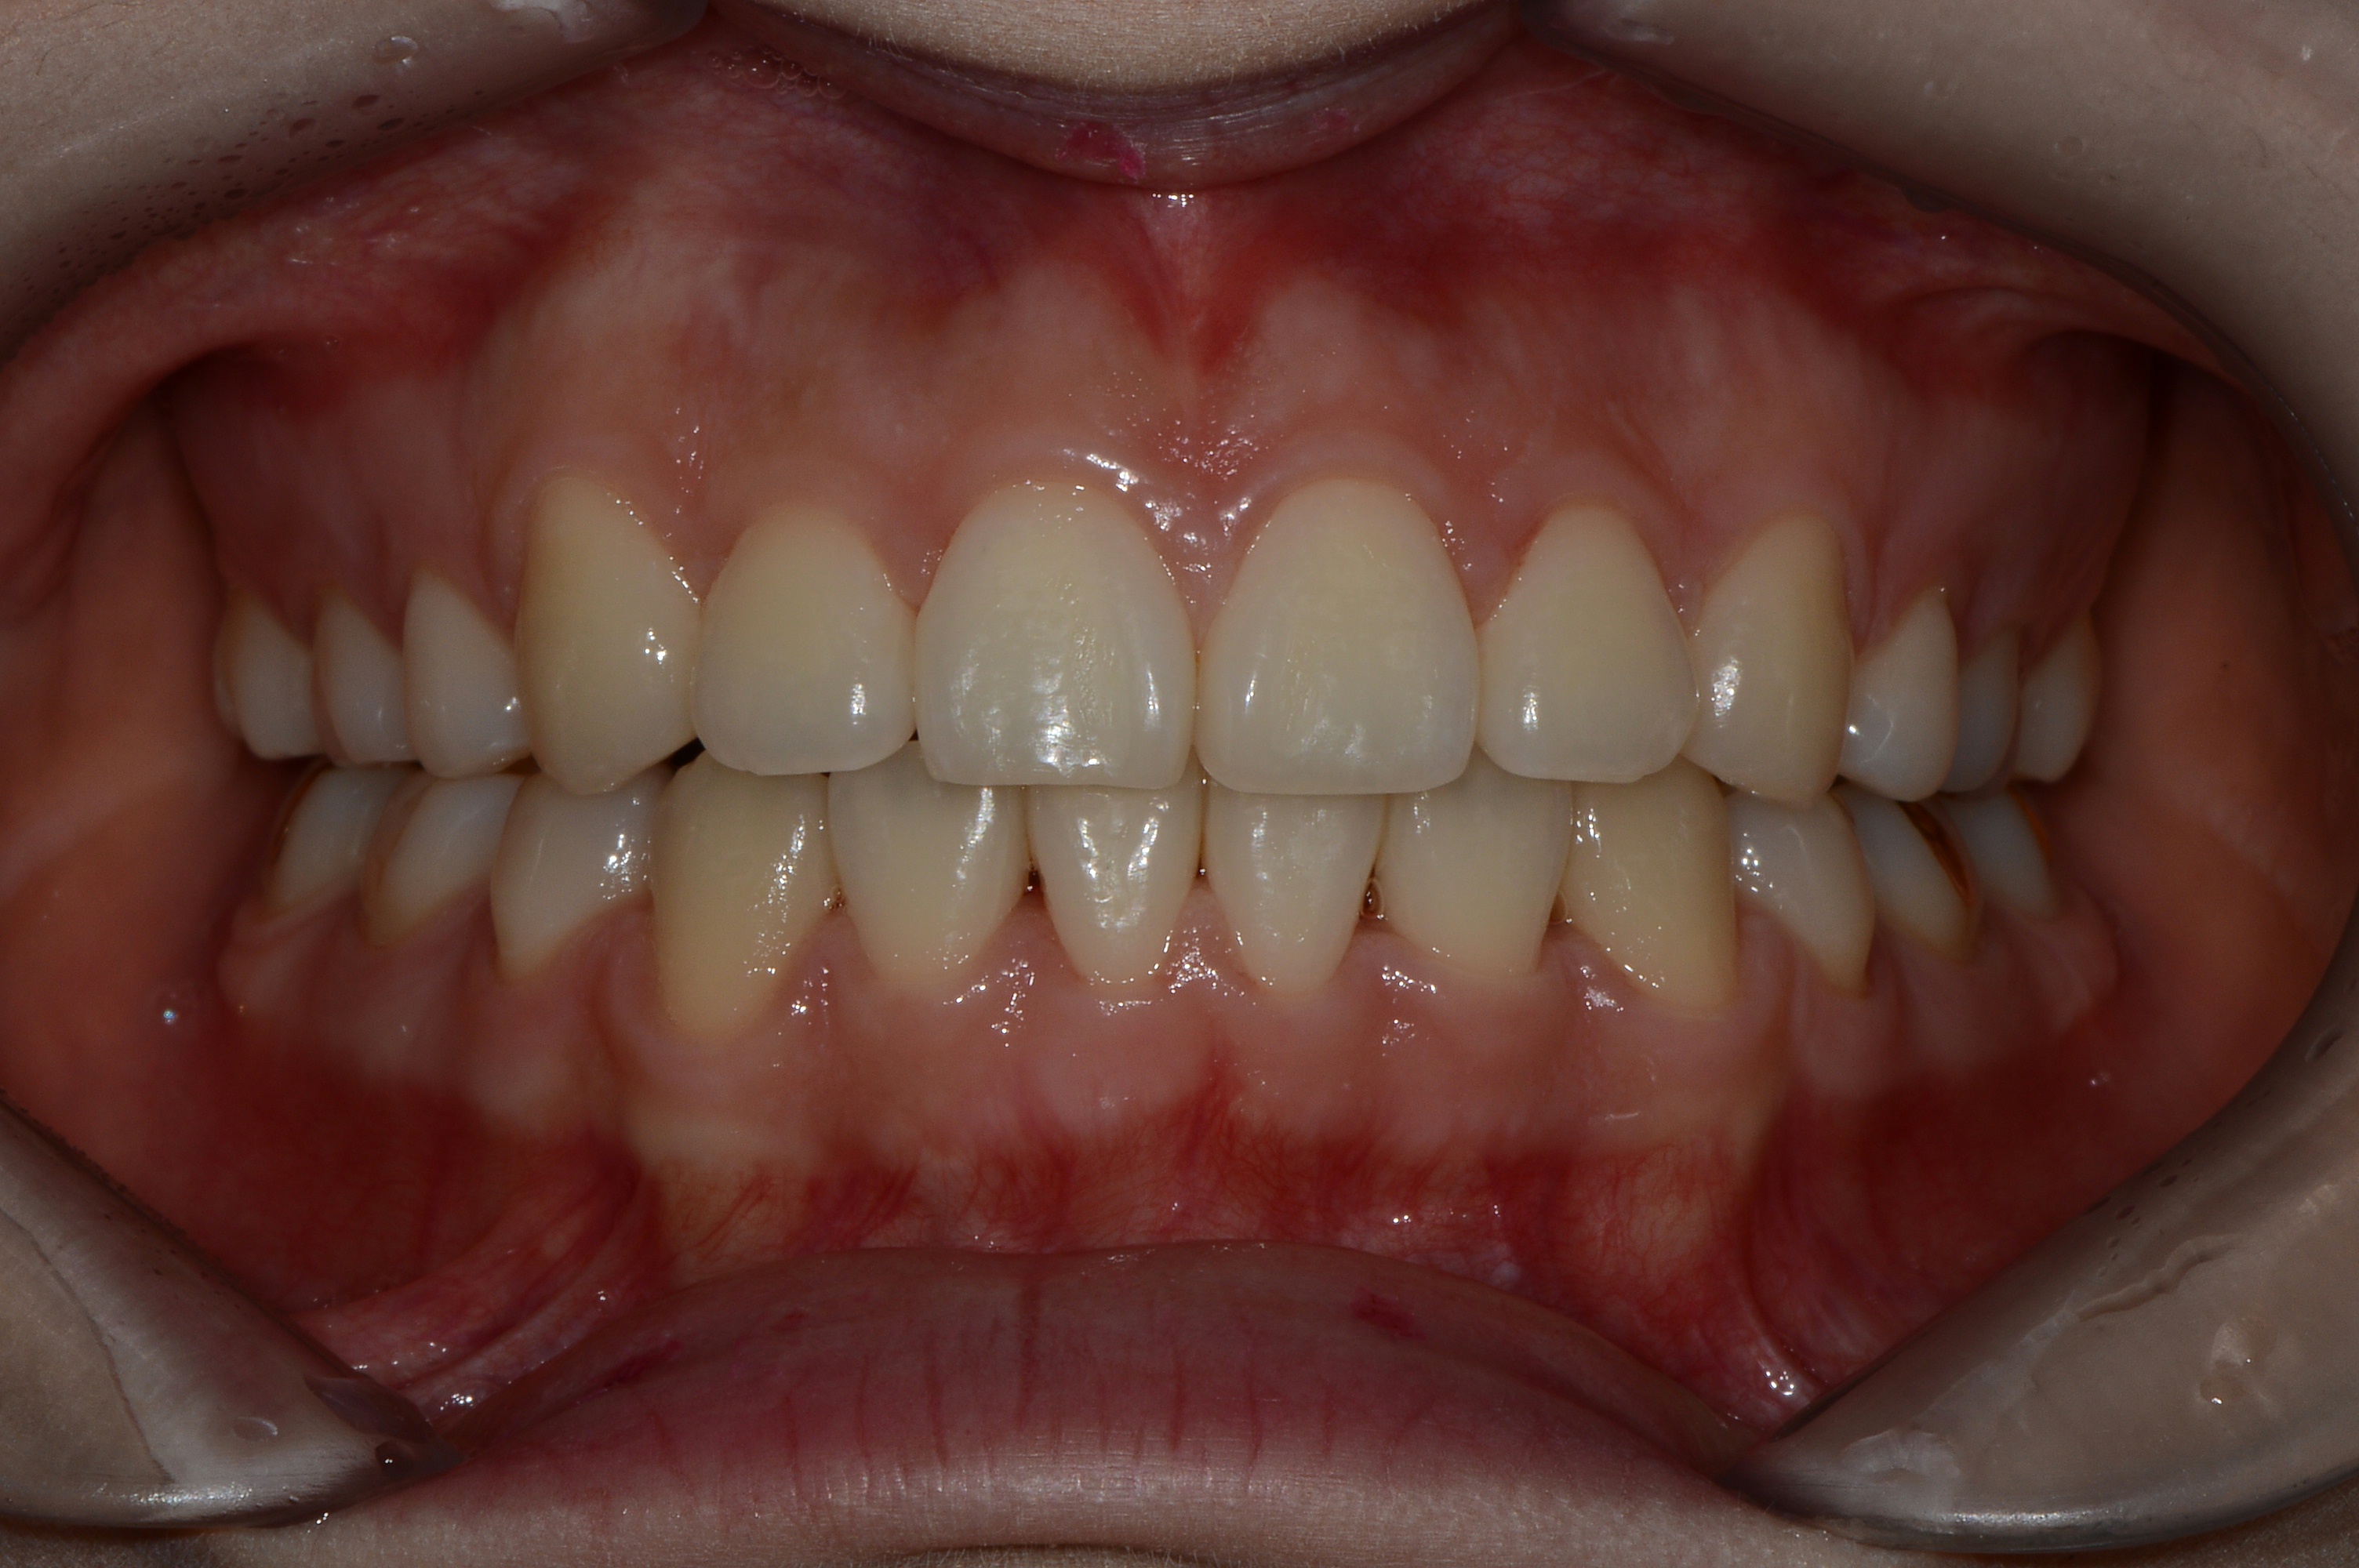

치료 후 사진입니다.